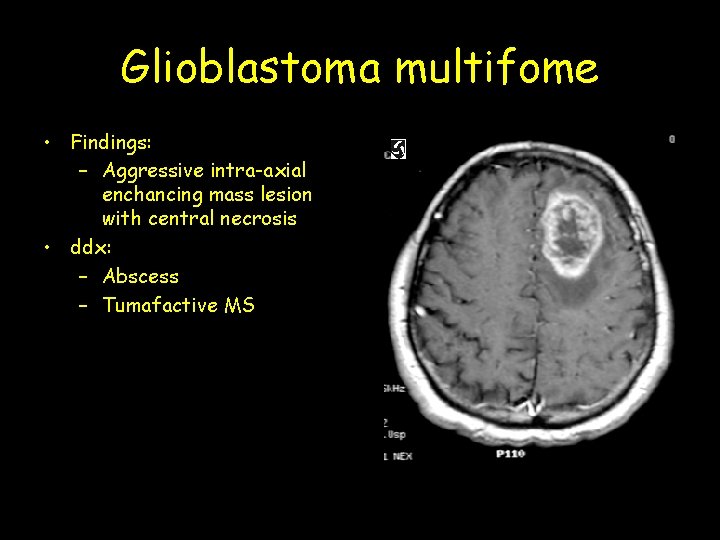

Glioblastoma multifome • Findings: – Aggressive intra-axial enchancing mass lesion with central necrosis • ddx: – Abscess – Tumafactive MS